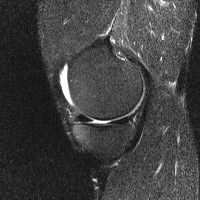

무릎 mri 간단히 봐주실 수 있으시나요 ㅠㅠ

안녕하세요 8년전 십자인대 수술하고 최근 무리한 운동에 무릎 불편감이 생겨서

mri 찍었습니다.

진단결과는 첫 찍은 병원에서 활액막염 이라는 진단을 받았습니다. 혹시 봐주실 수 있으실까요?

올라온 MRI가 단편적이라서 정확한 진단에 어려움이 있지만 십자인대에는 큰 이상이 있지는 않은것 같으며, 무릎관절내 물이 있는 것으로 보아 활액막염의 진단이 맞을 것 같습니다.

하지만 단편적인 영상이기 때문에 촬영병원에서 정확한 판독지 등을 받으시는 것이 좋겠습니다.